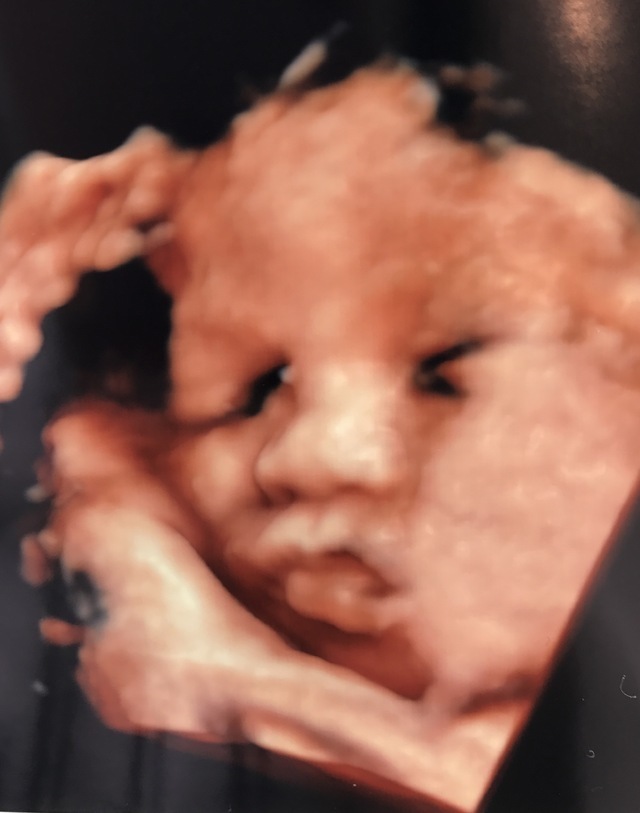

35週6日(35w6d・男の子)|ちゃさ さん(24歳)

エコー写真撮影時のエピソード:

いつも3Dまでしか見れないんですが、お金を払えば4Dが見れるということで撮りましたーっ^_^すごい鮮明に見えて、この時点でどっち似かわかるくらいです!!いろんな表情も見れてよかったですっ(●´ω`●)♬

これわ絶対撮るべきだと思いますよ〜〜!!!!!!!